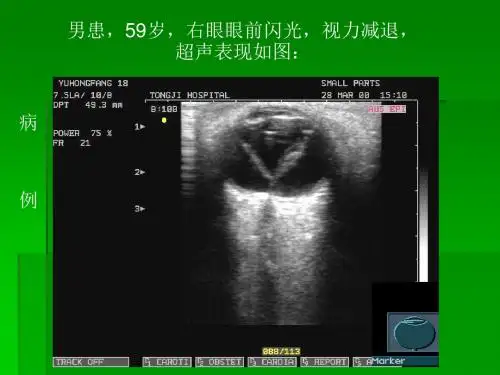

声像图表现

二维表现